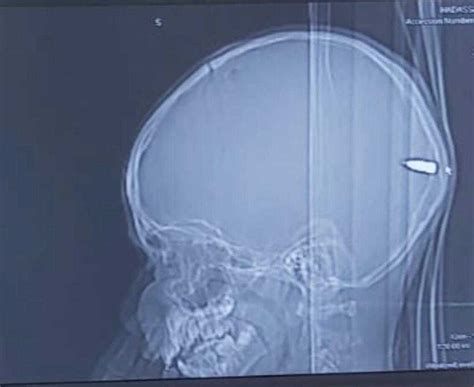

From a physical perspective, a bullet through the head can cause significant damage to the brain and its surrounding tissues. The impact of a bullet can cause a range of injuries, including lacerations, hemorrhages, and damage to brain cells and tissues. In some cases, the damage can be so severe that it can lead to death or permanent disability. However, in other cases, the brain may be able to recover from the injury, and the individual may be able to regain some or all of their cognitive and motor functions.